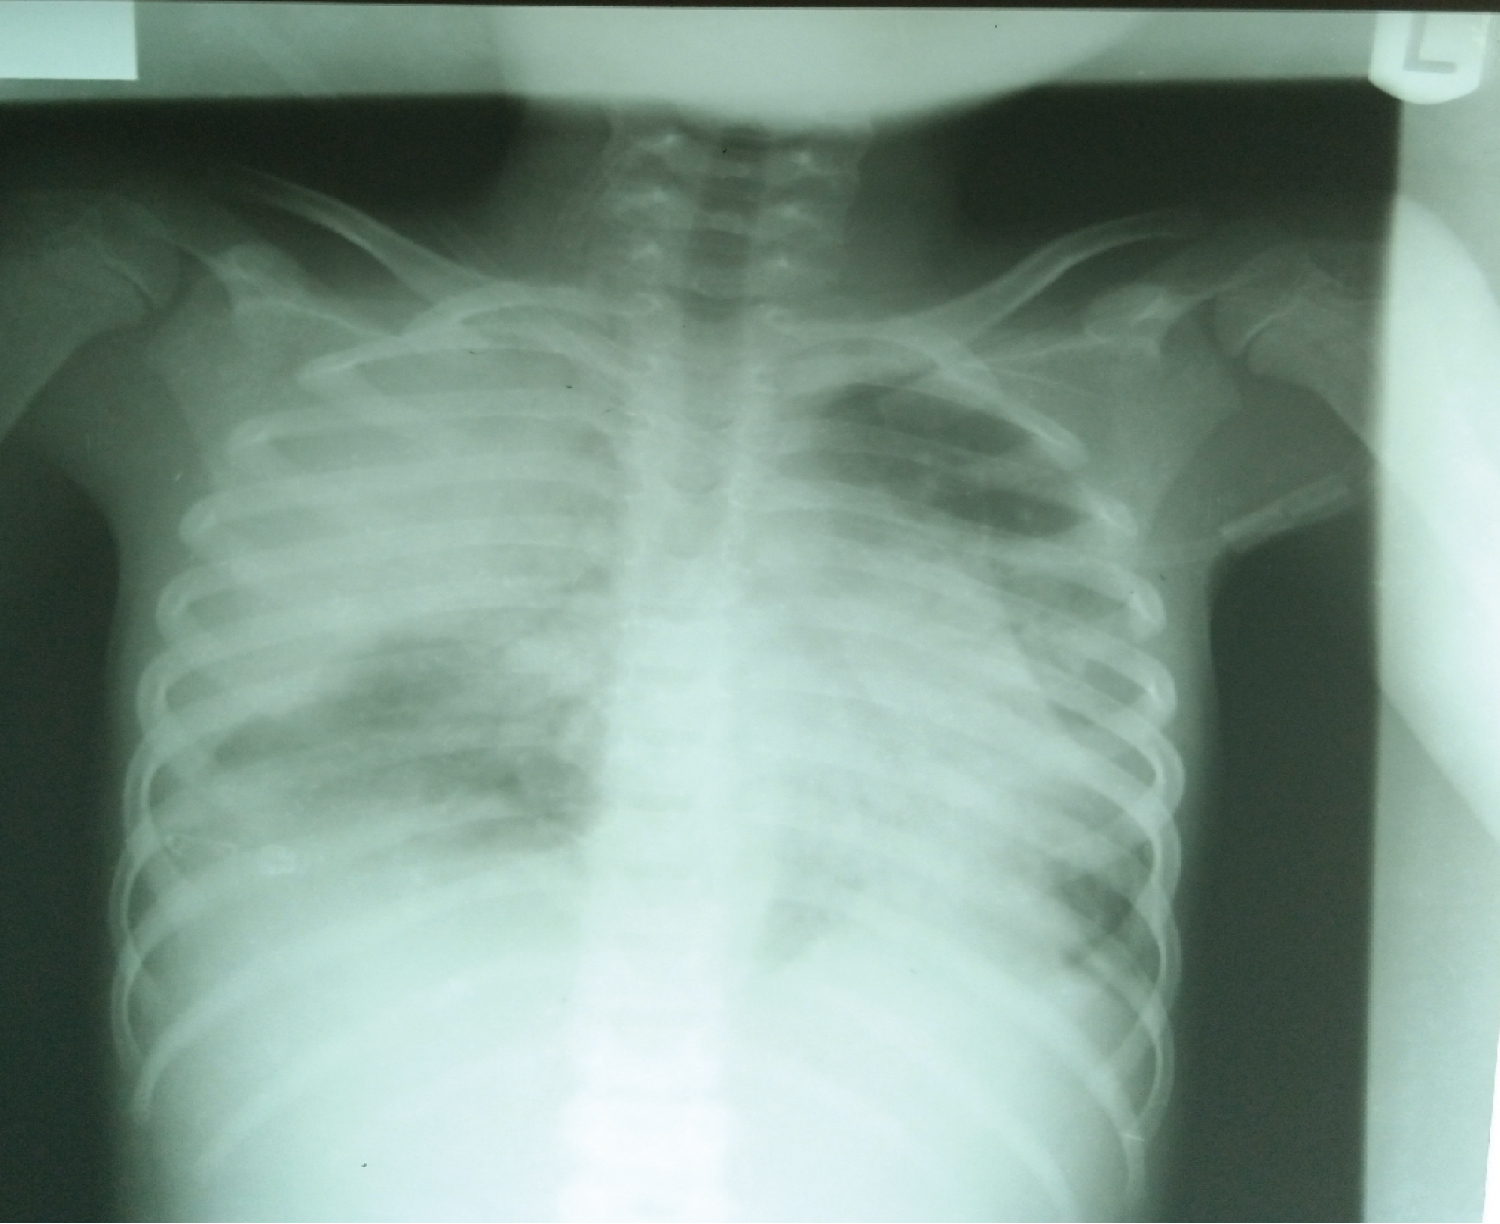

Chest X-ray (Figure 1) showed extensive patchy and ground glass air space opacifications with some peripheral distribution involving almost the entire right lung fields. Similar but to a lesser extent patchy opacity are seen involving the left lung fields more within the middle and lower lung zones. The diaphragmatic outlines are indistinct due to the aforementioned opacities. The cardiac size could not be measured due to the opacities which had silhouetted the cardiac borders.

Figure 1: Chest radiograph. View Figure 1

Her chest radiography findings of extensive patchy and ground glass air space opacifications with some peripheral distribution involving both lungs strengthened our suspicion of viral pneumonia most likely due to SARS-CoV-2. Although, there is no single feature of COVID-19 pneumonia on a chest radiograph that is specific or diagnostic but the published literature reveals general hallmarks of SARS-CoV-2 infections to include CXR findings of bilateral pulmonary infiltrates with a tendency toward the lung periphery [13,14]. Also Chest CT findings of bilateral and peripheral ground glass and consolidated opacities, with an absence of concomitant pulmonary nodules, cavitation, adenopathy and pleural effusions are generally considered as features of COVID-19 pneumonia [14]. Chest CT could not be done on account of the cost and it was not readily available.